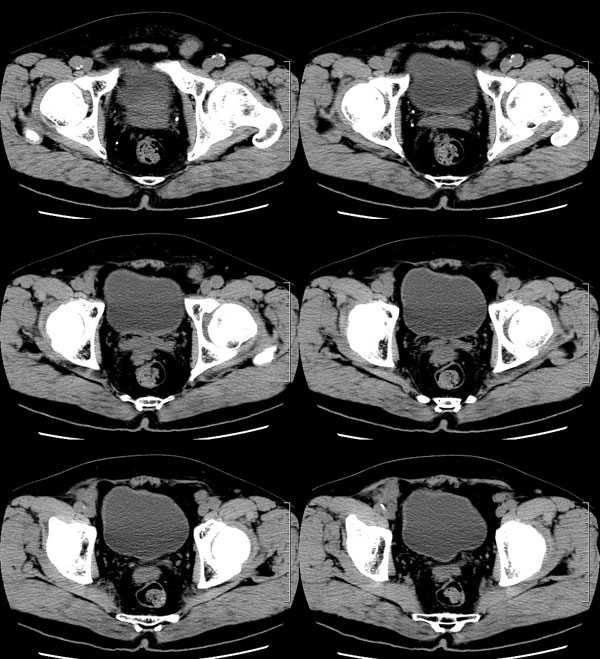

| 男性,69岁。自2个月前开始无意中发现左侧阴囊内一鸡蛋大小肿物,当时无伴疼痛等不适,未予重视。肿物逐渐增大,近段时间常伴左会阴部、腹股沟区牵扯不适,并于2周前在我院门诊行彩超检查提示“左侧附睾肿瘤可能,左侧睾丸鞘膜积液”。 专科检查:左侧阴囊肿大,其内可触及一鹅蛋大小肿物,表面光滑。肿物前部呈囊性感,后部质硬,按压无疼痛,无缩小,活动度良好。左侧睾丸未触及,透光试验(±)。                 王仕学发言:左侧睾丸见一密度不均肿块,边缘清楚,周围见水样密度影;考虑睾丸生殖细胞性肿瘤可能性大. 睾丸肿瘤占生殖系统肿瘤的3%-5%,占男性恶性肿瘤的0.5%-1.0%,其中生殖细胞性肿瘤占95%.睾丸肿瘤包括生殖细胞和非生殖细胞肿瘤两大类,前者占95%以上,后者不到5%.非生殖细胞肿瘤虽少见,但种类繁杂,主要有支持细胞、间质细胞和支持细胞-间质细胞瘤等功能性肿瘤,和间皮瘤、腺癌、横纹肌肉瘤、粘液性囊腺瘤、纤维上皮瘤、黑素神经外胚瘤、淋巴瘤等附属组织肿瘤。不同的病理类型的睾丸肿瘤发病率高峰不同,睾丸癌多发于35岁以前,精原细胞瘤发病高峰为30-35岁。精原细胞瘤约占睾丸肿瘤的60%,发病高峰在30-35岁。85%的患者睾丸有明显肿大,肿瘤局部侵犯力较低,肿瘤一般有明显界限。 手术:行“左侧附睾、睾丸、精索切除术”。 病理诊断:(左睾丸、附睾)肿物,为低分化腺癌。另送检(左精索远端)肿物,镜下亦为低分化腺癌。 免疫组化:ck(l)(++++)、cea(+++)、ca19-9(-)、psa(-)、plap(-)、p53(-)、vimentin(-)。 原贴地址:http://www.radinet.com.cn/forum_view.asp?forum_id=4&view_id=30707 |